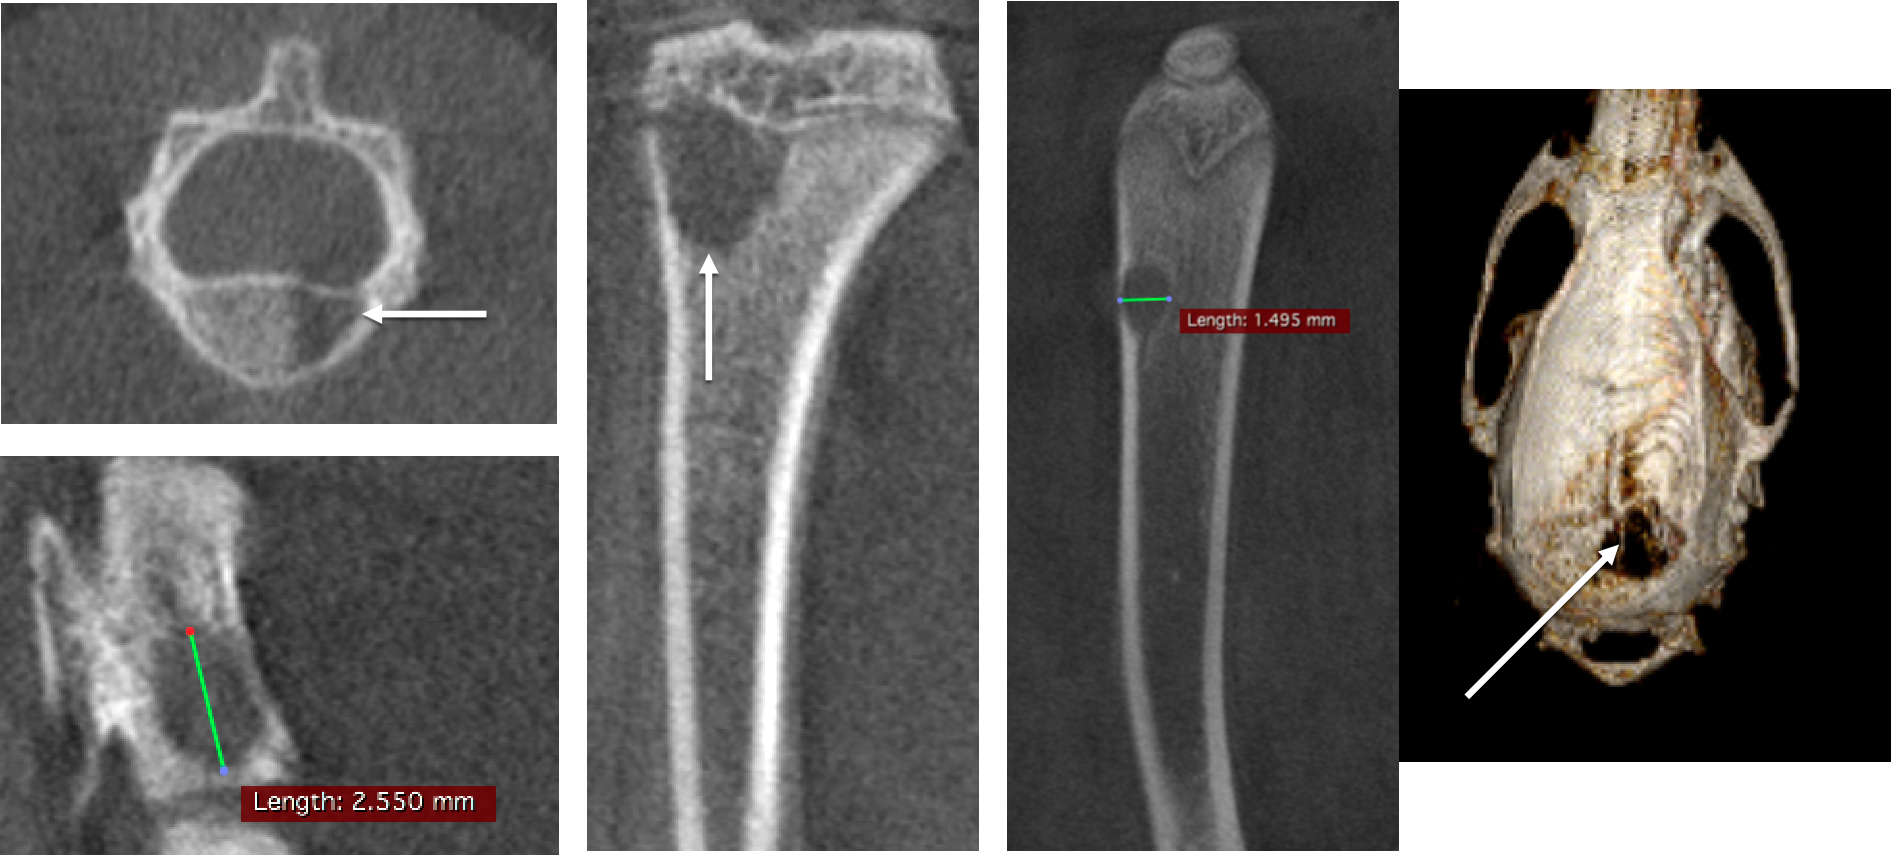

Bone tumor studies: In vivo CT in rats showed that the tumor caused brain and bone metastases, a large number of cavities in the bone, FDK reconstruction, 50µm voxel size.

In vivo measurement of rat tail vertebrae: high resolution ring acquisition, acquisition time: 2min3s, ISRA reconstruction, 50µm voxel size.

In vivo measurement of spinal vertebrae in rats: high definition ring acquisition, acquisition time: 4min, FDK reconstruction, 50 and 20µm voxel size.

Bone data processing with PMOD software: By selecting the region of interest (ROI) on the CT scan image for threshold segmentation and other operations, cortical bone (bone dense) and bone trabeculae (bone cancellous) can be segmulated and extracted into different tissue regions respectively, so as to study and analyze various morphological characteristics of them.